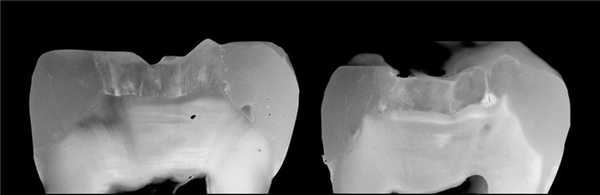

Фото 2. Результаты лечения дефектов ІІ класса: текучим композитом (1) и обычным композитом (2). Текучий композит позволяет добиться лучшей адаптации.

3. Послойное восстановления дефектов II класса

После восстановления контактной поверхности дефекта ІІ класса в полость вносят высоконаполненный текучий композит толщиной, как минимум, в 2 мм (фото 3). Цель данного этапа состоит в улучшении маргинальной адаптации в пришеечной области. Проксимальная стенка восстанавливается обычным наногибридным композитом для достижения надлежащих биомеханических характеристик реставрации в проекции маргинального гребня. После трансформации дефектов II класса в дефект І класса вносят порцию Tetric EvoFlow Bulk Fill с целью восстановления объема дентина. При этом толщина внесенного слоя не должна превышать 4 мм.

Фото 3. Схема внесения порций композита при ІІ классе дефектов. Текучий композит Tetric EvoFlow Bulk Fill может быть внесен за один этап (слой 1 и 3) при максимальной толщине слоя в 4 мм.